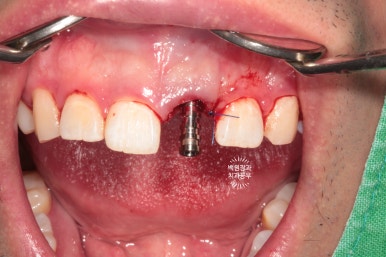

이를 뽑은 자리에 조심스럽게 오스템 BA 임플란트 고정체 (fixture)을 위치시킵니다.

최종 보철물을 만드는데 있어, 주변치아와의 관계를 고려한 임플란트의 위치와 깊이가 가장 중요하기에 많은 경험을 바탕으로 신중하게 해내야해요!!

잘 보시면 발치 즉시 임플란트 시행시 왜 뼈이식을 꼭 해야하는지 알 수있습니다.

지극히 상식적입니다. 제거된 치아 뿌리는 비정형적인 형태를 갖고 있지만, 우리가 사용하는 임플란트는 원기둥 형태이기 때문에 필연적으로 비어있는 공간이 생기기 때문이죠.

이를 발치한 곳 (=발치와)과 임플란트 사이의 공간에

국산 뼈이식 재료를 이용한 뼈이식을 시행하였습니다.

그 gap 부위에 뼈 이식재를 사용하여 꾹꾹 눌러담아 줍니다.